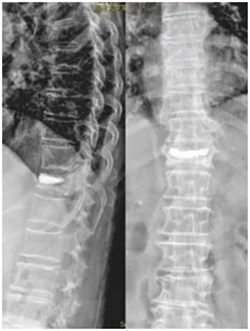

现在常用的是微创骨水泥手术,刘老太就是接受了这种治疗。骨科一病区科主任徐明杰和张鹏飞主治医生往她骨折的椎体里注入了一种叫“骨水泥”的材料,凝固后就能把压扁的骨头撑起来,快速稳定脊柱、缓解疼痛。

▲ 术后X线

这种手术伤口很小,恢复也快,大多数患者术后一两天就能下床活动,腰痛能明显缓解。